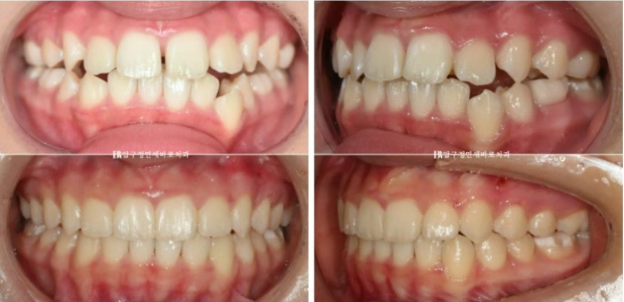

24.07

그리고 추가장치를 4달간 더 낀 후의 모습입니다.

중심선은 잘 맞아졌습니다.

교합도 좋습니다.

23.08~24.07

무엇보다 한쪽의 3급 어금니 교합관계는 1급이 되었습니다.

치료가 잘 끝났으니 1년간의 변화를 보겠습니다.

22.12~24.07

어린이 교정에 있어서 소아교정의 한계를 설명하기 보다는 어린이 환자지만 성인때 교정을 안 해도 될만큼 완벽한 교합 만들기를 목표로 진료합니다.